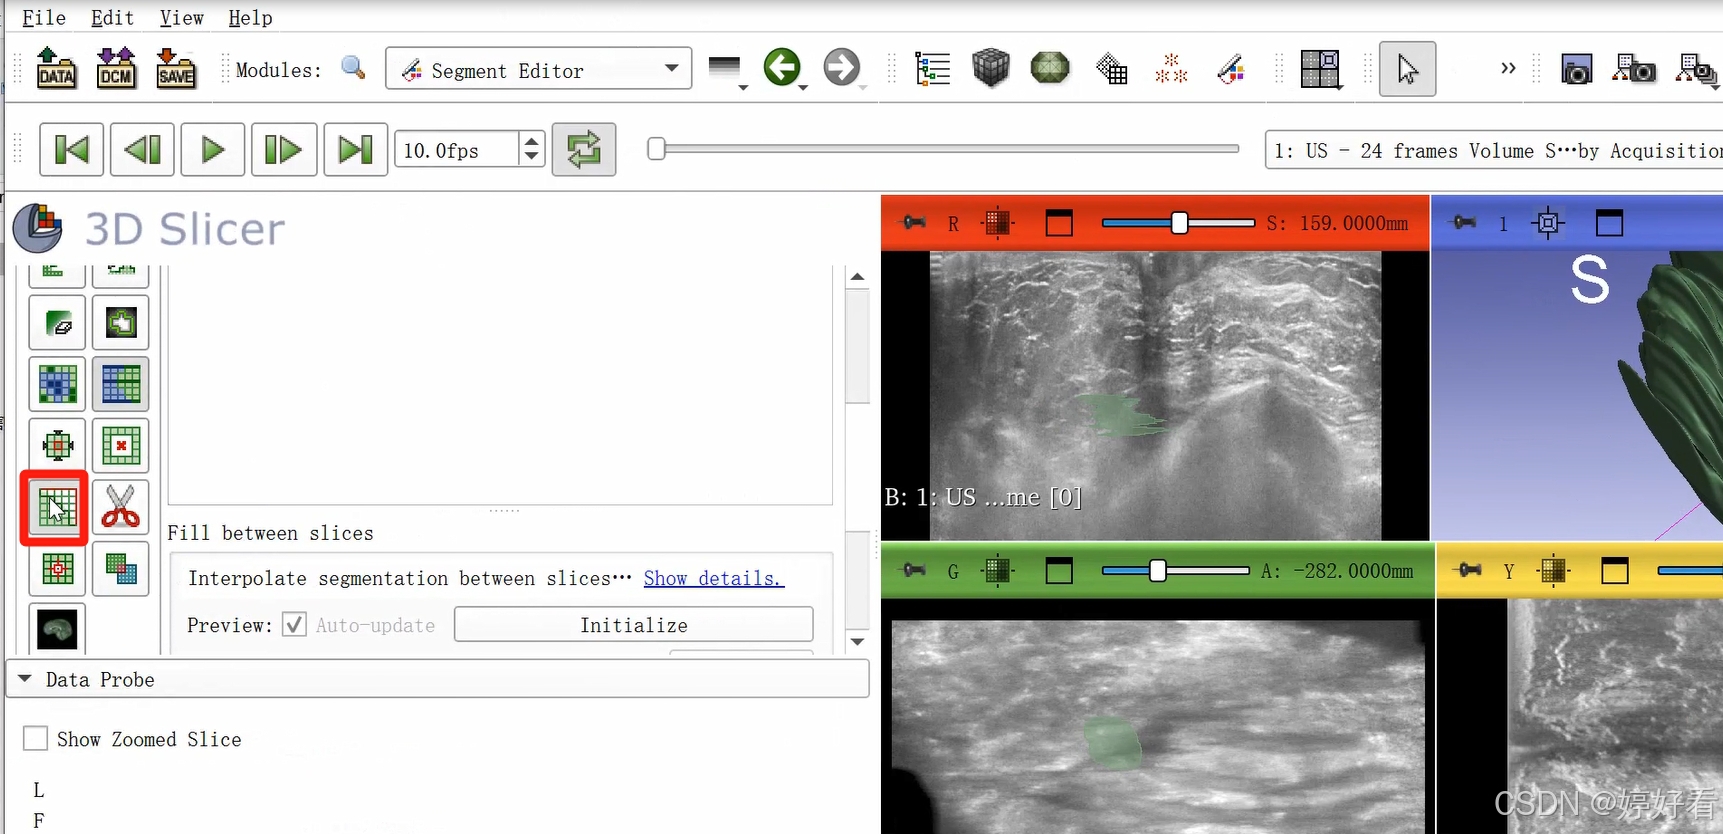

2.6 使用Fill between slices功能

上一步中完成的三维图像不是完整连续的三维图像,是一层一层的。Fill between slices这个功能可以自动填充每一层之间的间隙。选中Fill between slices,然后依次点击Initialize-Apply。